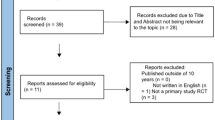

Due to the nascency of the field, we adopted a broad search strategy to capture all relevant articles. The search strategy was undertaken following the Preferred Reporting Items for Systematic Reviews and Meta-analyses (PRISMA) guideline [18]. This review was registered on the PROSPERO register (CRD42021276106).

A literature search of PubMed and OVID Medline databases was performed using the search query (“3D Printing” OR “Three-dimensional printing”) AND (“Robot Assisted Radical Prostatectomy” OR “Robotic Assisted Laparoscopic Prostatectomy”). No filters were placed on the search which included articles in all languages and a timeline from inception to 13th August 2021. An updated search was also performed on 1st January 2022. Additionally, reference lists of all screened articles were interrogated.

Inclusion and exclusion criteria

All articles published in English before the search date (1st January 2022) that reported data of interest were included in the review. Systematic and narrative reviews and conference abstracts that were later published were excluded. Abstracts were individually screened by all authors for eligibility and any disagreements were resolved by discussion until a consensus was reached. No automated tools were used in this process. Articles deemed eligible for this review were categorised into surgical planning, simulation, and patient engagement.

Eight articles met inclusion criteria for this review. Six were identified via database searches, to which a further two articles were “snowballed” via a thorough appraisal of the reference list of known publications. The following data were extracted from all eligible articles; authors, study type, study size, software used, 3D printing technique, anatomy demonstrated and cost. Given the heterogeneity of the studies, a meta-analysis was not performed. Specific data relating to each study’s endpoints and aims were extracted for the review discussion.

Two authors (J.CB. and S.O.) assessed each article for risk bias. Given all articles were non-randomised trials, the ROBINS-I tool was used [19]. Supplementary Table 1 shows the bias score given to each article (see Fig. 2).

Eight articles were identified for inclusion. Of these articles, five publications (62.5%) reported on the utility of 3D printed models for NS-RARP planning. Two publications (25%) utilised 3D printed prostate models for robotic console simulation, and two publications (25%) used the models as a tool to engage patients. There were five prospective single centre studies, one case series, one technical report and one letter to the editor.

A summary of included publications is contained within Table 1. Due to the sparsity of articles concerning the intersection of these two new technologies, all included studies are discussed below (see Fig. 3).